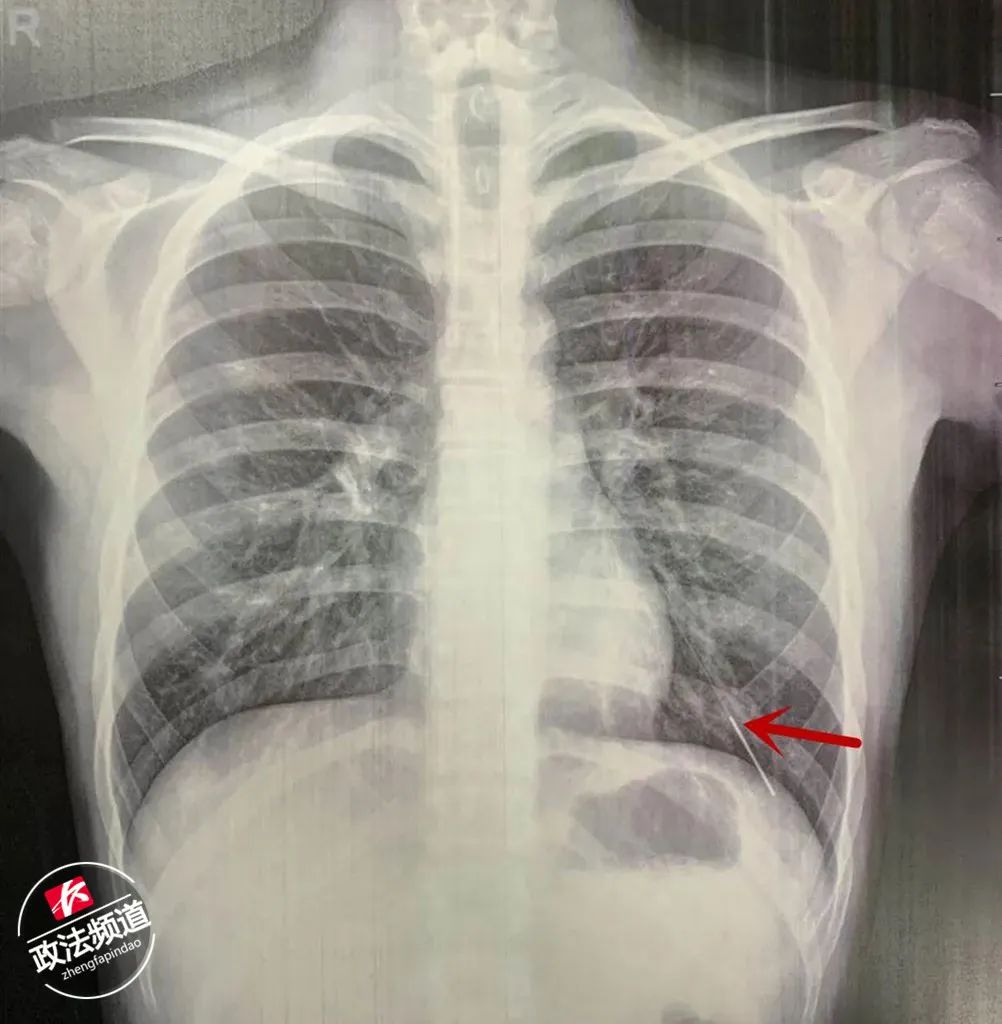

▲CT顯示,針灸針掉入小迪的左肺

媽媽許女士慌忙帶小迪到家附近醫(yī)院就診,CT顯示,7厘米長的針灸針已經(jīng)扎進(jìn)了小迪的左下肺。